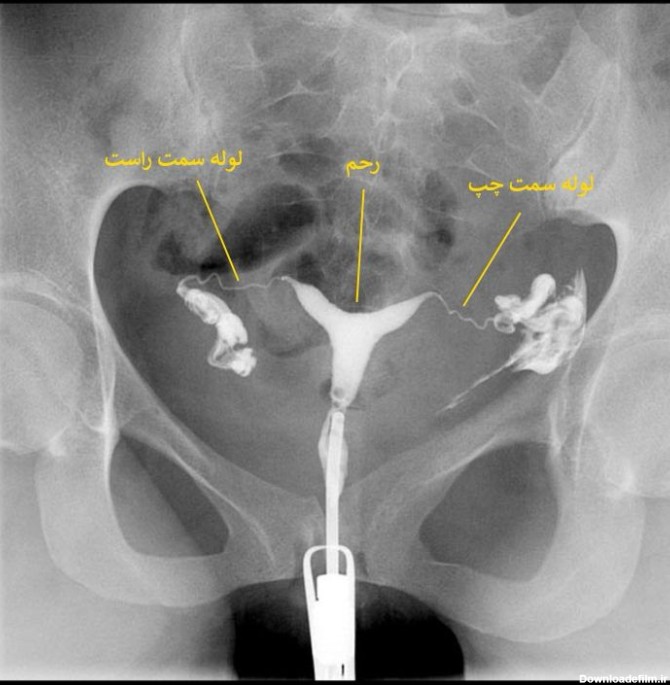

عکس رنگی رحم با بیهوشی در تبریز

تصویربرداری رنگی رحم برای زنانی انجام می شود که دارای مشکلات باروری می باشند.یکی از رایج ترین مشکلات ناباروری ...

الزاما در عکسبرداری رنگی رحم فرد بیهوش نمیشود، بنا به صلاحدید پزشک و انتخاب بیمار تصمیمگیری میشود که آیا بیمار تحت بیهوشی قرار گیرد یا خیر؟

عکس رنگی رحم با بیهوشی یا بدون درد یکی از خواسته های بانوان است که از حدود شانزده سال پیش توسط دکتر مقدس زاده در مرکز پرتو طب آزما قم در حال انجام است.